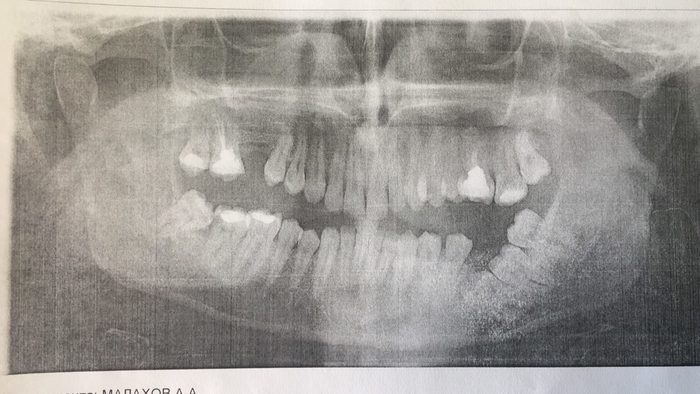

Мне удалили зубы мудрости по левой стороне. Нижняя 8мерка лежала глубоко, и мне сверлили челюсть, как я поняла, что бы достать зуб, потому, что он никак не хотел выходить. Так же удалили верхний зуб, но проще и быстрее.

Обе нижних восьмёрки у меня росли (а одна всё ещё растёт) повёрнутыми на 90 градусов, упираясь в корни 7-х зубов. Причём верхние растут точно также, но в противоположную сторону и, максимум, будут некрасиво торчать в сторону горла, если вообще когда-нибудь решат вылезти.

А вот нижняя, зараза, решила сквозь десну таки проклюнуться и судяпо тому, насколько сильно на рентгене зуб был вдавлен в корень 7-го было принято решение удалять, пока из-за него слишком сильно не пострадала 7-ка.